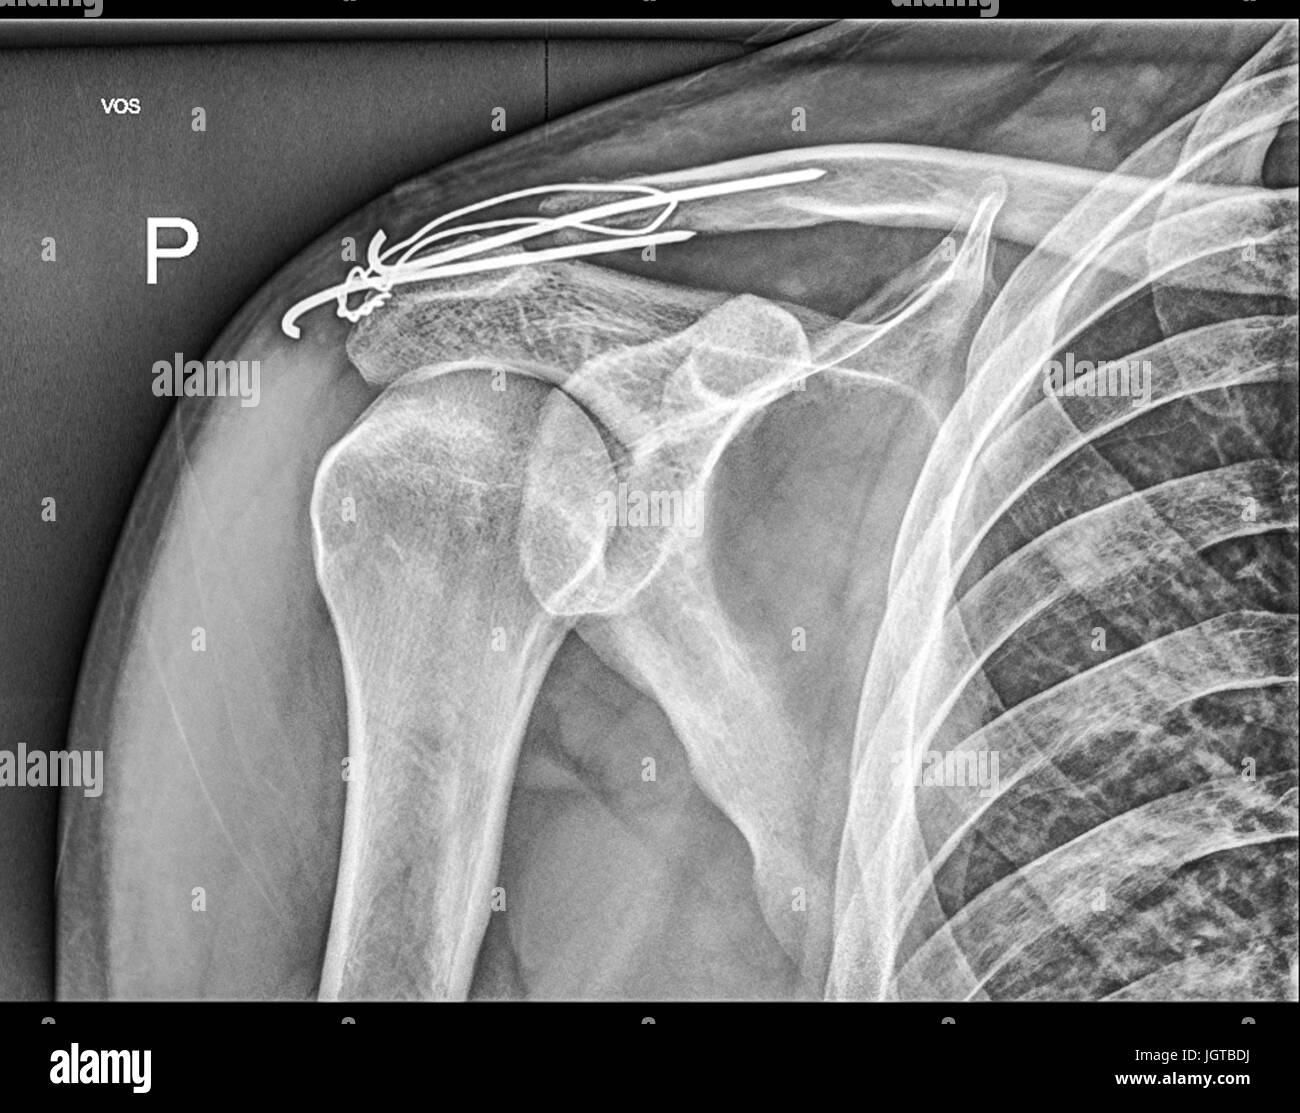

From www.alamyimages.fr

Broken Clavicle Banque d'image et photos Alamy Clavicule Cassee Temps Guerison la durée varie en fonction de plusieurs facteurs, peut aller de 6 à 12 semaines (3 mois). La reprise du sport peut être plus longue. ⏱️ temps de guérison et récupération après une fracture de la clavicule. le temps de guérison d’une clavicule cassé est d’environ 6 semaines. Tous ces délais sont raccourcis chez l’enfant et l’adolescent.. Clavicule Cassee Temps Guerison.